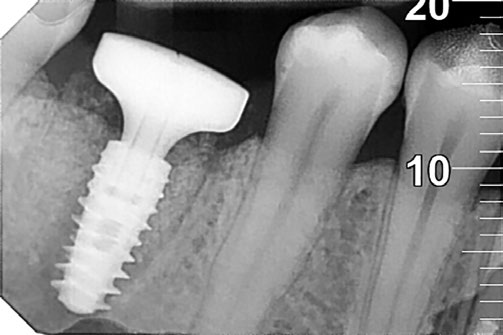

En este artículo, describo cómo utilizamos un enfoque innovador para la colocación de implantes postextracción, combinando cirugía guiada y flujo digital para mejorar la precisión, la estética y la preservación de los tejidos.

El uso de tecnología avanzada en el tratamiento permitió no solo una colocación precisa del implante, sino también una integración más rápida y un perfil de emergencia adecuado para el paciente. Además, sistemas como Healfit de Anthogyr jugaron un papel crucial en la cicatrización de los tejidos blandos, garantizando resultados funcionales y estéticos a largo plazo.